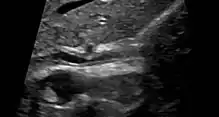

Historically, a cholangiogram would be obtained via endoscopic retrograde cholangiopancreatography (ERCP), which typically reveals "beading" (alternating strictures and dilation) of the bile ducts inside and/or outside the liver. Currently, the preferred option for diagnostic cholangiography, given its noninvasive yet highly accurate nature, is magnetic resonance cholangiopancreatography (MRCP), a magnetic resonance imaging technique. MRCP has unique strengths, including high spatial resolution, and can even be used to visualize the biliary tract of small animal models of PSC.[21]